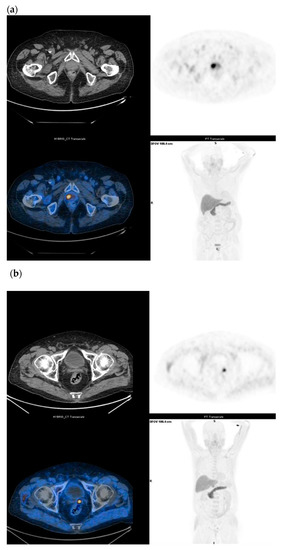

18F-Fluciclovine is a synthetic amino acid used as a PET tracer for PCa. Cell uptake is a system mediated transport of neutral amino acids such as LAT 1 and ASCT2 across mammalian cell membranes, which are overexpressed in many cancer cells, including those from prostate cancer. Once inside the cell, 18F-Fluciclovine is not metabolized and is incorporated into proteins and only a small part is excreted in the urinary system. Similar to other tracers, the PET tracer 18F-Fluciclovine is a non-specific uptake by benign inflammatory prostatic tissue and in a variety of other malignancies. The aim of the study was to evaluate the diagnostic and specific sensitivity of 18F-Fluciclovine for the diagnosis of primary cancer, pre-operative LN staging, for the recovery of prostate disease and for the evaluation of bone metastases. In several studies, 18F-Fluciclovine PET/CT shows a higher uptake in intra-prostatic tumor foci than in normal prostate tissue (Figure 5a,b). However, 18F-Fluciclovine uptake in tumors is similar to that in BPH (benign prostate hyperplastic) nodules [23,26]. The Food and Drug Administration (FDA) and European Medicines Agency (EMA) have approved 18F-Fluciclovine in the recurrent setting only [28]. After definitive treatment for prostate cancer, patients are routinely followed up with serum PSA level. 18F-Fluciclovine is highly useful in the detection of recurrent prostate cancer, even in the presence of non-conclusive conventional imaging. In fact, CT or MRI scans may not detect or accurately characterize the biochemical relapse at the earliest stage [29]. However, functional imaging with Choline or Fluciclovine PET/CT associated with multi-parametric MRI (MP-MR) seems to be the most valuable technique in the detection of prostate cancer relapse [23]. These functional images are cost-effectiveness when PSA doubling time is short. 18F-Fluciclovine PET/CT shows detection rates of 72.0%, 83.3%, and 100% at PSA levels <1, 1–2. and >2 ng/mL, respectively [19]. In comparison with MP-MR, many studies concluded that 18F-Fluciclovine imaging for the evaluation of primary PCa was limited. Delayed imaging (20–28 min) could improve diagnostic performance for the characterization of primary cancer and can help guide biopsy in high-risk disease [17,23]. A study compared prospectively 18F-Fluciclovine and PSMA PET/CT scans for localizing recurrence of PCa after prostatectomy in patients with a PSA level <2.0 ng/mL. PSMA PET/CT detection rates for pelvic and extra-pelvic metastasis were higher than those for 18F-Flucicloviune PET/CT [10]. Other results, obtained in a more heterogeneous and at higher risk population, showed a better detection rate for 18F-Fluciclovine compared to PSMA for the detection of prostate bed recurrences in areas close to the bladder (37.9% and 27.6%, respectively) [30]. The lower urinary excretion of 18F-Flucicloviune PET compared to PSMA PET might be the explanation of this finding. However, PET/CT findings validation is not always feasible, especially in the recurrent setting. Nevertheless, it is well established that 18F-Fluciclovine is highly useful in the detection of recurrent prostate cancer, when conventional bone scan and CT and/or MRI imaging are negative [29]. Our meta-analysis study showed promising results in terms of sensitivity and specificity of 18F-Fluciclovine PET/CT, as recently reported in other meta-analysis recently published [31,32,33]. High specificity values have been observed for preoperative LN staging (almost 100%); acceptable (although lower) pooled specificity (68%) was obtained for the detection of PCa recurrence in terms of local recurrence and nodal localization. Discrepancy may be a consequence of a smaller number of studies included in meta-analysis of preoperative LN staging (which may have somehow reduced the statistical power of this sub-analysis) compared to the recurrent setting. The validation of positive findings still represents a challenge for medical imaging in oncology. In pre-surgery setting, a more accurate approach can be designed, and PET results can be validated by histology. Generally, lesion- or region-based validation is preferable and (especially for lymph node metastasis) positive PET lesions are compared with surgery templates. On the contrary, in the recurrent setting, the standard of truth is generally composite. Histological confirmation of metastatic sites is not often feasible due to ethical and practical reasons. Thus, PET findings are generally validated with informative conventional imaging that might have lower diagnostic accuracy compared to new generation imaging. Further validation can be obtained by complete PSA response in subjects treated with image-guided therapy. This heterogeneity might explain the different specificity observed in primary staging vs. recurrent setting.

Figure 5.

(a) Staging in un-operated prostate cancer under drug treatment (Gleason Score: 4 + 3) and with a moderate increase in serum PSA (1.67 ng/mL); 18F-Fluciclovine PET/CT shows intense parenchymal uptake (SUVmax 15) in the right paramedian site of the prostate. (b) Biochemical recurrence in prostate cancer (Gleason Score: 4 + 4) subjected to radical HIFU treatment three years ago and with PSA elevation (3.3 ng/mL); 18F-Fluciclovine PET/CT shows a focal uptake in the left prostatic lodge (SUV max 7).